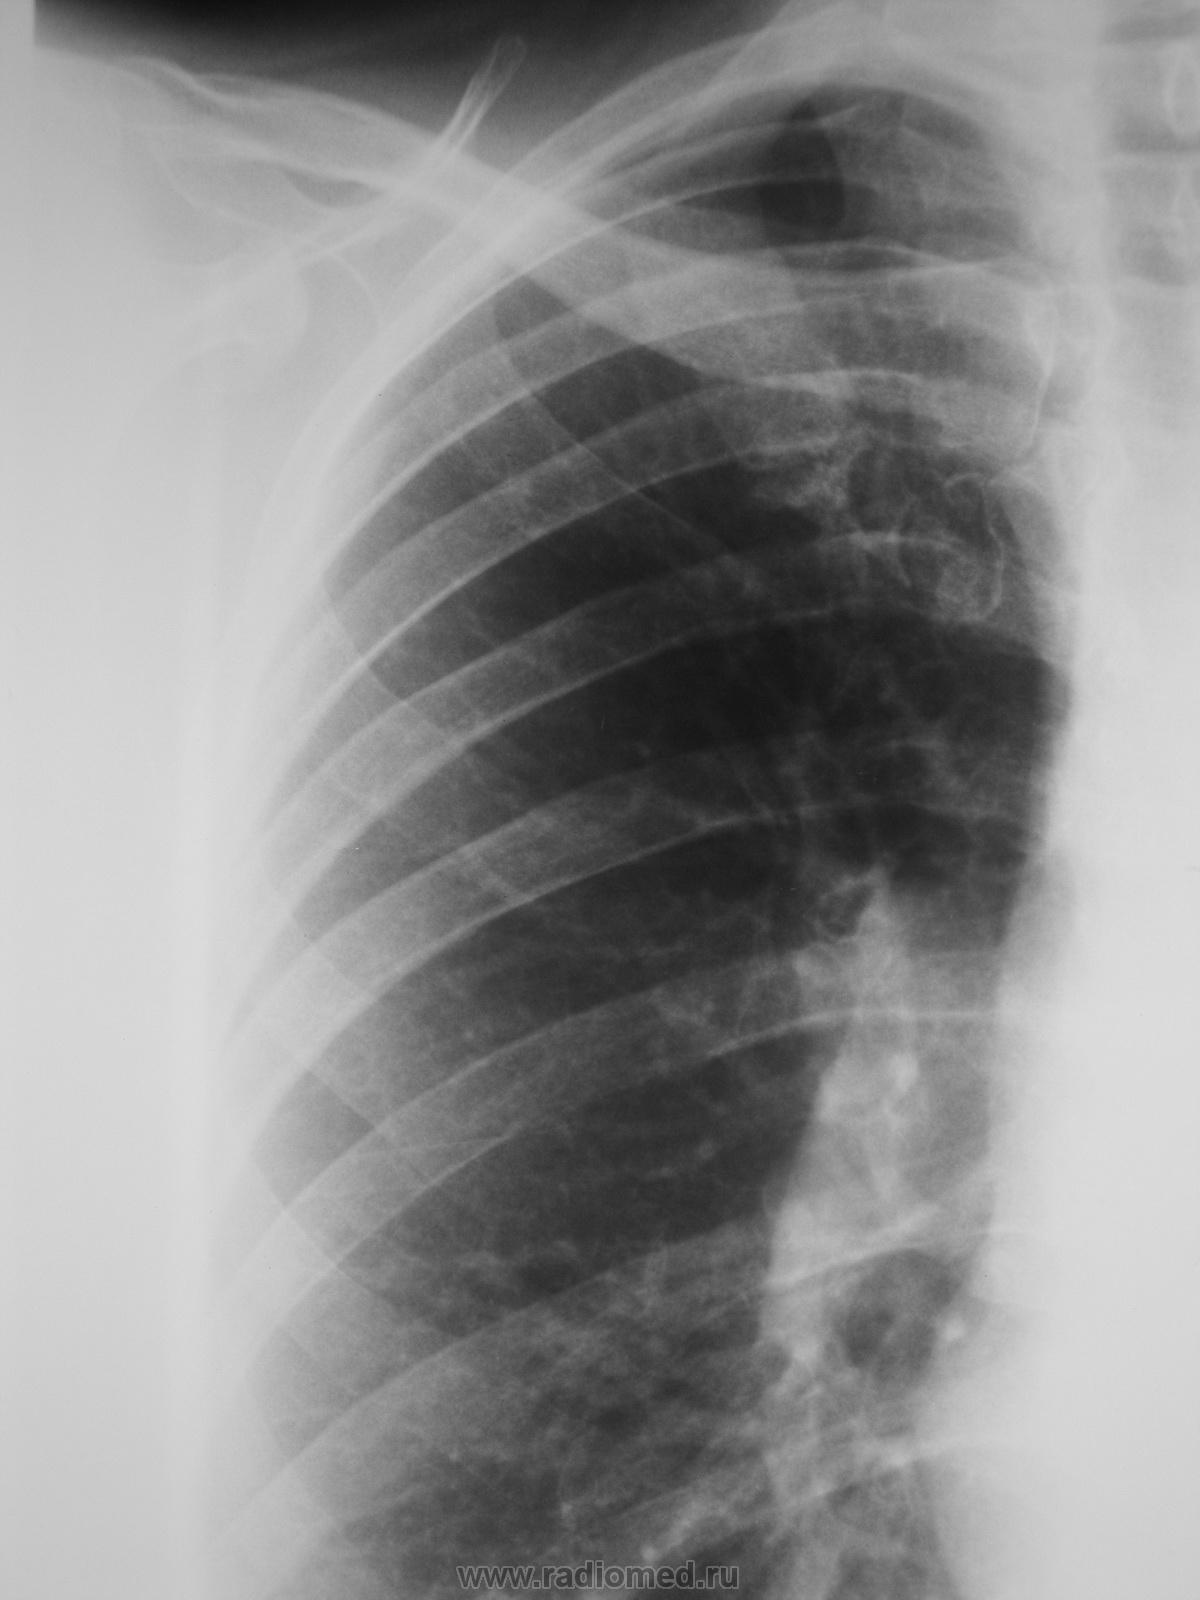

Извините коллеги забыл откопировать обычную сегодняшнюю обзорную прямую..- томограммы от 14.04.2011 вашему вниманию. Обзорка за июнь прошлого года . В анаменезе в 2010 июль опрерирована Sa в фиброзном узле матки.

заполненную ретенционную бронхиальную кисту легкого

Ретенционные кисты должны иметь "свою историю", они за год не растут...тут годы и годы нужны. В первую очередь исключайте метастатическое поражение.

+1.Возможно,она имела историю и в данном случае: зачастую на Rg виден только фиброз.к-ый можно пропустить,а уж Tg приоткрывает слои))) Типичная заполненная ретенционная киста